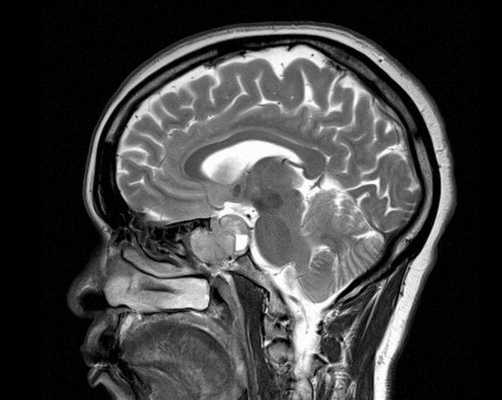

Снимок МРТ головного мозга в двух проекциях

Магнитно-резонансная томография обеспечивает сканирование области турецкого седла в трех взаимно перпендикулярных проекциях. Послойные монохромные снимки детализируют состояние анатомических структур зоны интереса, показывая малейшие изменения формы, размера, строения рассматриваемого объекта.

В процессе анализа снимков, полученных в результате магнитно-резонансной томографии, визуализируют структуру железы и окружающих тканей, прослеживается форма и размеры гипофиза. Малейшие изменения строения будут замечены врачами и позволят диагностировать аденому, независимо от ее размера.

При помощи снимков, полученных в результате проведения лабораторного обследования, прослеживается размер железы, форма, структура гипофиза и окружающих тканей. МРТ позволяет диагностировать даже малейшие изменения в нормальной работе железы, независимо от её размеров, локализации и формы.